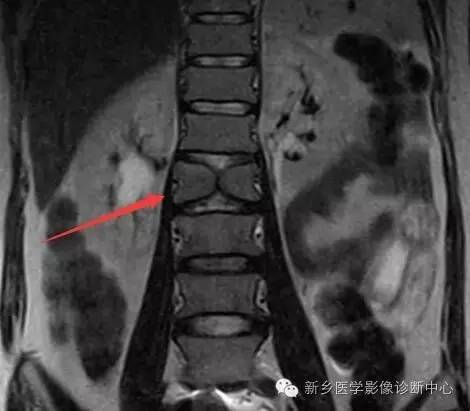

半椎体:椎体的一半缺如或发育不全,半椎体较正常椎体小,圆形、椭圆形、楔形,位于中线一侧;胸椎半椎体多合并有并肋畸形

脊椎椎体畸形(半椎体、蝴蝶椎)